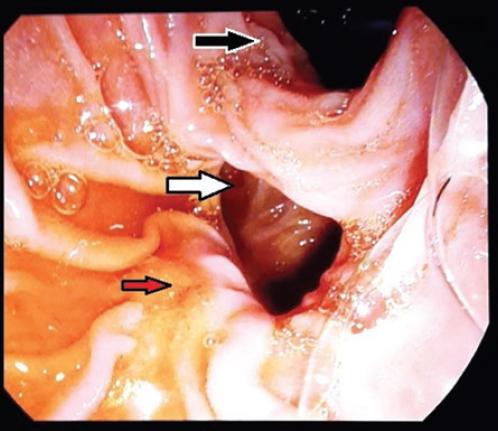

Ante dichos hallazgos se solicita duodenoscopia más colangiografía retrógrada endoscópica (CPRE) con la finalidad de realizar esfinterotomía, descompresión y drenaje de la vía biliar. Durante el procedimiento no es posible canular el ámpula de Vater, por un lito impactado en ella (Fig. 3) y divertículo Noda C, Boix IIa, además de ámpula fibrótica (Fig. 4) (Vídeo 1).

Figura 4 Visión retroversión endoscópica en colangiopancreatografía retrógrada endoscópica que muestra el divertículo (flecha blanca), el ámpula de Vater (flecha roja) y la primera porción del duodeno (flecha negra).